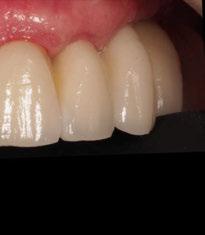

4. Fase protésica provisional

Una vez colocados los pilares provisionales de titanio, se adaptó la férula pick-up modificada y se verificó su correcto asentamiento de los pilares a través de los orificios de ésta. A continuación, se recapturó la férula a los pilares de titanio mediante resina acrílica autopolimerizable (Enamel Temp

Plus®) y, una vez polimerizada, se tomó un registro de mordida, se desatornillaron los pilares y se retiraron de boca. Seguidamente, se atornillaron los análogos verificando que no hubiera movilidad de ningún pilar y se envió al laboratorio para el acabado y pulido final, eliminando todo el soporte y añadiendo un refuerzo metálico por palatino. En boca, se colocaron los tapones de cicatrización de los transepiteliales y se le explicaron las recomendaciones postquirúrgicas y medicación necesaria. Instruimos al laboratorio a dejar los perfiles de emergencia lo más estrechos posibles y los pónticos ovoides entrando unos 3 mm en cada alveolo a fin de preservar la arquitectura gingival presente.

A las 24 horas se citó al paciente nuevamente, se atornilló el provisional en boca y se realizó una

Figura 24. Provisional finalizado tras acabado y pulido en el laboratorio.

Figura 25. Provisional finalizado tras acabado y pulido en el laboratorio.

Figura 26. Entrega del provisional de carga inmediata a las 24 horas.

Figura 27. Ortopantomografía del provisional atornillado en boca para verificar ajuste.

ortopantomografía de verificación del ajuste pasivo de todos los implantes. Por último, tapamos las chimeneas con teflón y resina provisional y se chequeó nuevamente la oclusión, dando nuevamente las instrucciones de higiene y mantenimiento de la prótesis provisional (Figuras 24-27).